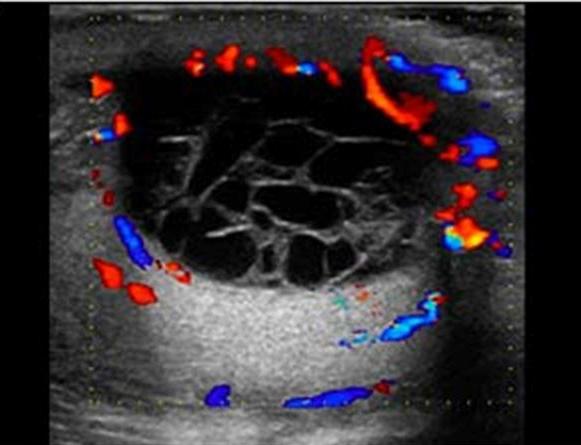

left side

most common correctible cause of male infertility

Varicocele

left side

most common correctible cause of male infertility

Varicocele